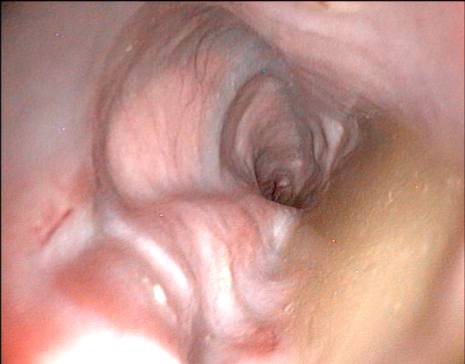

- Срыгивание (регургитация) — это пассивный процесс. Пища выходит без усилий, часто неожиданно для самого питомца, через несколько минут после еды. Она выглядит как непереваренная «колбаска» в слизистой оболочке, потому что не успела попасть в желудок